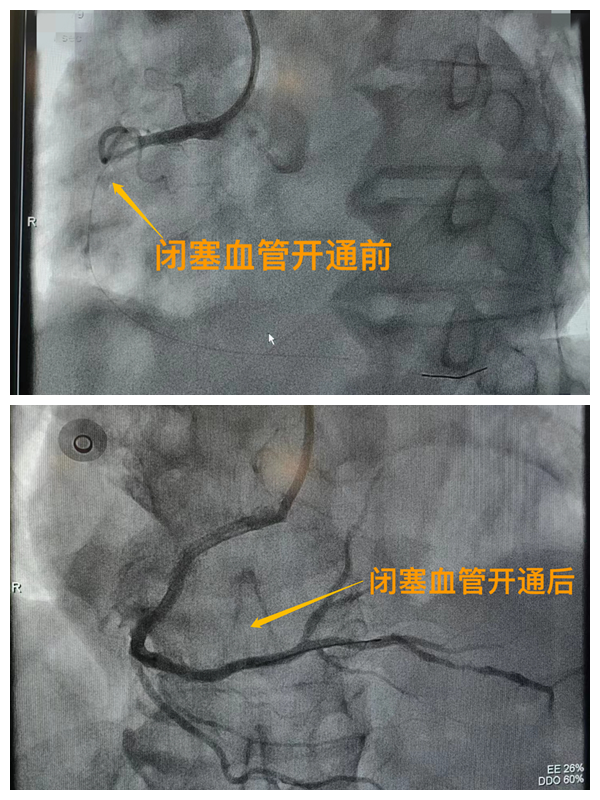

活動(dòng)開(kāi)始前,院長(zhǎng)王瑾對(duì)現(xiàn)場(chǎng)群眾進(jìn)行了健康科普宣講,她以近期醫(yī)院救治的多例急性心肌梗死患者的癥狀、發(fā)展、急救、手術(shù)、康復(fù)全流程情況為例,向小區(qū)群眾講述了心梗的發(fā)病癥狀和院前急救注意事項(xiàng),以及要及時(shí)通過(guò)120送至專(zhuān)業(yè)的胸痛中心開(kāi)展科學(xué)、規(guī)范的急救手術(shù)的必要性,講述了心?;颊咿D(zhuǎn)危為安的全過(guò)程,得到了廣大群眾的共鳴與好評(píng)。

市二院胸痛中心于2021年12月23日通過(guò)中國(guó)胸痛中心認(rèn)證,成為國(guó)家級(jí)胸痛中心,先后開(kāi)展了冠心病的介入診療、心律失常的心內(nèi)電生理檢查及射頻消融治療、永久起搏器植入、先天性心臟病的介入封堵及臨時(shí)起搏器植入、主動(dòng)脈內(nèi)球囊反搏治療等,完成心臟介入手術(shù)3000余例。多次創(chuàng)造從入院至行急診介入手術(shù)開(kāi)通血管(入門(mén)-導(dǎo)絲通過(guò))30分鐘以?xún)?nèi)記錄,極大保證了患者的生命安全,提高了預(yù)后質(zhì)量,挽救了眾多急性心?;颊叩纳?。(尹紅婭       張   靜)